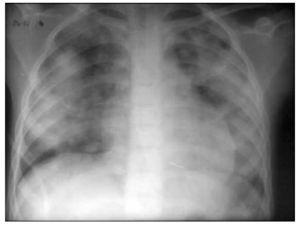

Diagnóstico. La radiología torácica revela infiltrados alveolares con patrón difuso (fig. 7) o focal que pueden ser confirmados con la TC torácica. En las vasculitis sistémicas, las enfermedades del tejido conectivo y el síndrome de Goodpasture aparece proteinuria y alteraciones en el sedimento urinario indicativas de glomerulonefritis, así como aumento de la creatinina.

Figura 7. Imagen radiológica que muestra un infiltrado alveolar difuso en una hemorragia alveolar.